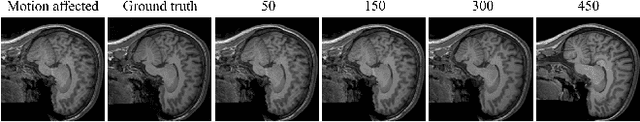

Magnetic Resonance Imaging generally requires long exposure times, while being sensitive to patient motion, resulting in artifacts in the acquired images, which may hinder their diagnostic relevance. Despite research efforts to decrease the acquisition time, and designing efficient acquisition sequences, motion artifacts are still a persistent problem, pushing toward the need for the development of automatic motion artifact correction techniques. Recently, diffusion models have been proposed as a solution for the task at hand. While diffusion models can produce high-quality reconstructions, they are also susceptible to hallucination, which poses risks in diagnostic applications. In this study, we critically evaluate the use of diffusion models for correcting motion artifacts in 2D brain MRI scans. Using a popular benchmark dataset, we compare a diffusion model-based approach with state-of-the-art methods consisting of Unets trained in a supervised fashion on motion-affected images to reconstruct ground truth motion-free images. Our findings reveal mixed results: diffusion models can produce accurate predictions or generate harmful hallucinations in this context, depending on data heterogeneity and the acquisition planes considered as input.